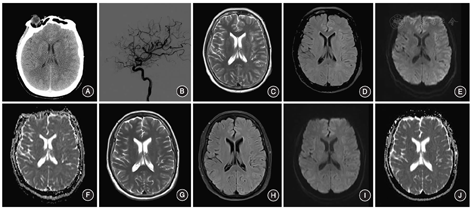

例2 男,52岁。因"发现颅内动脉瘤1年余,头痛8 d"入院。1年前体检时发现前交通动脉动脉瘤,无肢体活动障碍。8 d前出现头痛,于我院行DSA检查,提示前交通动脉动脉瘤,建议行血管内治疗,患者拒绝,自动出院。1 d前再发头痛,伴恶心,无视力模糊、肢体活动障碍等。入院体检未见明显异常。既往原发性高血压病史1年余,最高血压为180/110 mm Hg,口服厄贝沙坦片(每次150 mg,1次/d),血压控制可。糖尿病病史近1年,服用二甲双胍片(每次0.5 g,2次/d),血糖控制可。入院后给予双联抗血小板药物、控制血糖和血压等药物治疗。入院后第3天,行支架辅助弹簧圈栓塞颅内动脉瘤术(图2A,B)。术后2 h,患者出现言语不利,右侧肢体无力。体检:意识清楚,运动性失语,右上肢肌力Ⅱ级,右下肢肌力Ⅲ级。头颅CT未见明显出血(图2C,D),MRI未见明显异常。再次DSA检查未见脑动脉闭塞,与术后即刻比较,可见明显末梢血管痉挛。血常规、凝血功能、肝肾功能、心肌酶、C反应蛋白、血糖等实验室检查均未见明显异常。给予补液、控制血压、脱水药物及糖皮质激素等治疗。术后1 d,患者出现嗜睡,DWI序列显示左侧额、顶、颞、枕叶皮质高信号,呈"花边征"特点(图2 E~H)。考虑CIE可能性大,给予糖皮质激素1 000 mg冲击,同时补液、控制血压及应用白蛋白等治疗。术后2 d,患者出现四肢抽搐、口唇紫绀,症状持续约1 min;双侧瞳孔直径为4 mm,对光反射消失。给予地西泮、丙戊酸及甘露醇等治疗。症状缓解后患者自行睁眼,查体不配合,瞳孔反射正常,右下肢巴彬斯基征(+)。后患者多次癫痫发作,给予抗癫痫药物对症治疗。常规血液检查及丙戊酸药物浓度等均未见明显异常。术后4 d,患者出现精神亢奋、谵语,言语不利及右侧肢体无力症状好转;右侧肢体肌力Ⅳ级;头颅MRI与前相比,额、顶、颞、枕叶皮质未见异常信号(图2I~L),头颅CT未见明显异常;给予激素减量。术后5 d,患者言语不利、右侧肢体无力明显好转,抽搐未再发;右上肢肌力Ⅴ级,右下肢肌力Ⅳ级。术后9 d症状完全缓解,查体未见明显异常。术后1个月随访患者未诉不适。

此外,该2例患者DWI均显示"花边征"的特点,而既往文献报道中少见;与其他文献报道一致的是,影像学表现为以T2WI、T2-FLAIR、DWI为主的高信号,ADC无明显异常信号,且完全可逆[6]。受累区域与血管内操作的血管分布区一致,提示CIE与血管内操作及对比剂直接相关。考虑到患者行颅内动脉瘤栓塞术前DSA检查均未出现过敏反应及其他不适,进一步提示局部对比剂浓度可能与CIE的关系更为密切,与既往认为的高渗对比剂更易诱发CIE的结论一致[7]。